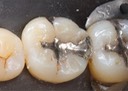

Joe Cha #18 amalgam removal